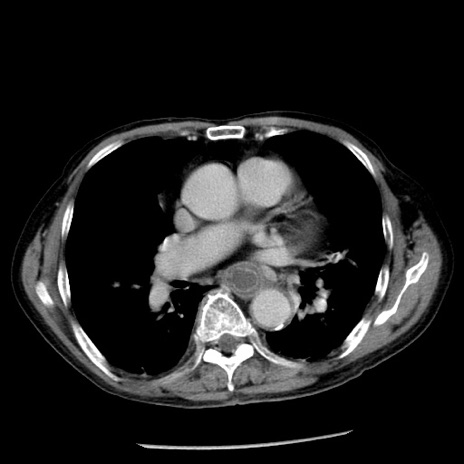

冠状断像

症例26(横断像)

【症例】80歳代男性

【主訴】嘔吐

【現病歴】昨晩2回嘔吐あり、今朝になっても嘔吐あり。来院。

【既往歴】胃潰瘍

【身体所見】意識清明、BT 37.6℃、BP 166/95mmHg、HR 100bpm、SpO2 97%、腹部:平坦・軟、腸蠕動音聴取良好、圧痛なし。

【データ】WBC 21900、CRP 1.46